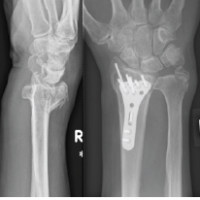

The primary objective of this study was to assess the effectiveness of external fixation (with optional K-wire pinning) in managing comminuted intra-articular distal radius fractures. Our findings support the hypothesis that external fixation provides good to excellent outcomes[Fig. 3-7] in cases where ORIF may pose technical difficulties, longer operative time, and higher soft tissue morbidity.

- Excellent functional outcomes (DASH score): Restoration of upper-limb function was consistently observed[Fig.3-6]

- Radiological maintenance (Sarmiento score): Near-anatomical alignment was preserved in most cases[Fig. 7]